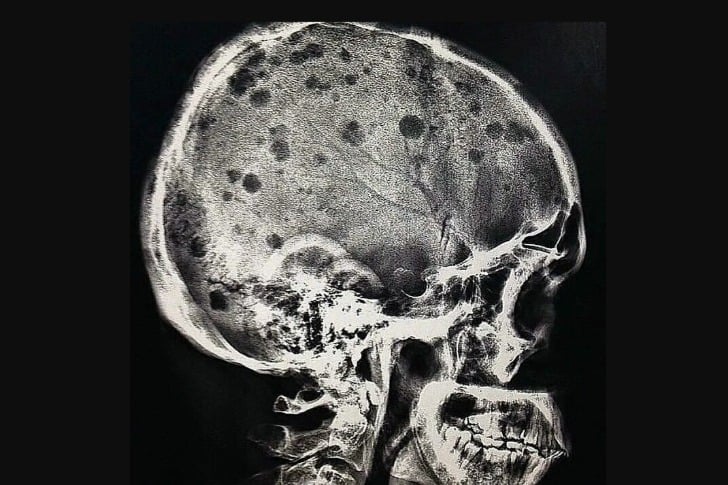

#32 Un patient atteint de myélome multiple

L’aspect radiographique classique du myélome multiple est celui de lésions multiples, petites, bien circonscrites, lytiques, « à l’emporte-pièce » et rondes au niveau du crâne, de la colonne vertébrale et du bassin. Le motif des lésions radiotransparentes lytiques ou « à l’emporte-pièce » sur le crâne a été décrit comme ressemblant à des gouttes de pluie frappant une surface et éclaboussant.